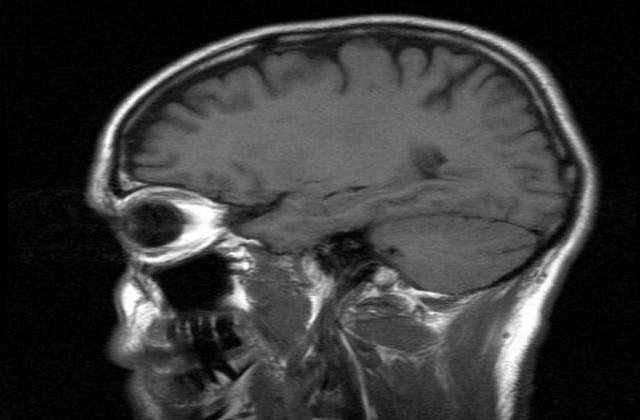

„Incercarea de a descifra misterele mintii au preocupat oamenii de stiinta pret de secole si continua sa ne preocupe si in prezent, cand bunastarea mentala continua sa fie un subiect presant in societate. Aceasta expozitie arată cat de mult am progresat in ceea ce priveste intelegerea mintii umane si cum au evoluat tratamentele pentru problemele mentale de-a lungul ultimelor trei secole”, sustine muzeograful Phill Loring.

Impartita in patru episoade intre anii 1780 si 2014, acest gen de expozitie urmareste descoperirile esentiale din domeniul stiintei si intelegerea creierului uman.